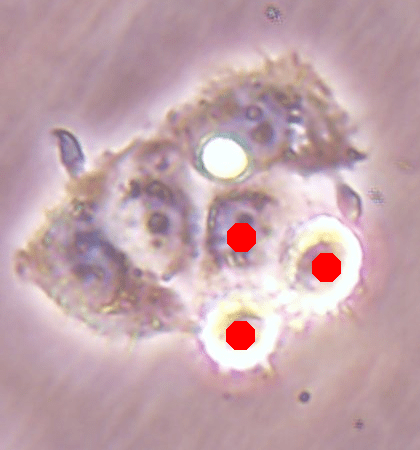

Before the advances in deep learning, the traditional approach for cell detection/segmentation is to employ low-level handcrafted features, reflecting color, edge, and shape characteristics of cells. This approach has given promising results when the features are defined properly, as a good representation of the visual cell characteristics. On the other hand, these characteristics may change from one cell type to another (see Fig. 1) and new features need to be defined to meet the cell characteristics of a new type. Additionally, when there exists heterogeneity in the visual characteristics of the same cell type, using a single model may not be sufficient to detect all cells of this type, particularly for cancer cells which are exploited more in high throughput screening.

![]() |

| (a) | (b) | (c) |

We test our DeepDistance model on three datasets, each of which consists of live cell images of a different cell line. They are the CAMA-1, MDA-MB-453, and MDA-MB-468 human breast cancer cell lines. The images in all datasets were acquired at magnification and pixel resolution. An example image from each dataset is shown in Fig. 1. As seen in this figure, cells might be visually different within and across different cell lines.